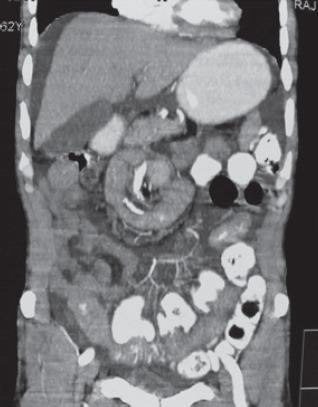

The incidence of the diverticulum of the small bowel varies from 0.2-1.3% in autopsy studies to 2.3% when assessed on enteroclysis. It occurs mostly in patients in the 6 decade of their life. Of all the small bowel diverticuli, jejunal diverticulum is the most common type. This rare entity is usually asymptomatic. However, they may cause chronic non-specific symptoms for a long period of time like dyspepsia, chronic postprandial pain, nausea, vomiting, borborgymi, alternating diarrhoea and constipation, weight loss, anaemia, steatorrhea or rarely lead to complications like haemorrhage, obstruction, perforation. Obstruction can be due to enterolith, adhesions, intussusception, and volvulus. The condition is difficult to diagnose because patients are generally presented with symptoms that mimic other diseases. It is important for clinicians to have awareness of this entity. Here, we present a case of multiple jejunal diverticuli with a history of repeated attacks of diverticulitis over past 20 years, which were misdiagnosed and now presented with intestinal obstruction due to volvulus of the involved segment along with mesentery around its axis. Resection of the diverticuli segment of jejunum was done with end-to-end jejuno-jejunal anastomosis. The patient is asymptomatic since 10 months of follow-up.

小肠憩室的发生率在尸检研究中为0.2%-1.3%,而在小肠灌肠检查时评估为2.3%。它大多发生在60岁左右的患者中。在所有小肠憩室中,空肠憩室是最常见的类型。这种罕见的病症通常无症状。然而,它们可能会长期引起慢性非特异性症状,如消化不良、慢性餐后疼痛、恶心、呕吐、腹鸣、腹泻与便秘交替、体重减轻、贫血、脂肪泻,或很少导致出血、梗阻、穿孔等并发症。梗阻可能是由于肠石、粘连、肠套叠和肠扭转引起的。这种病症很难诊断,因为患者通常表现出类似其他疾病的症状。临床医生了解这种病症很重要。在此,我们报告一例有20年反复憩室炎发作史的多发空肠憩室病例,该病例曾被误诊,现在因受累肠段连同其系膜围绕其轴扭转而出现肠梗阻。对空肠憩室段进行了切除,并进行了端端空肠吻合术。随访10个月以来,患者无症状。